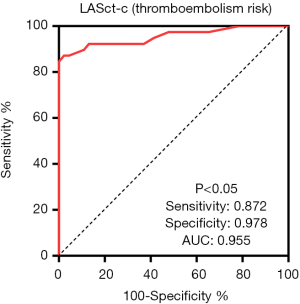

Diagnostic efficacy of LASct-c for the factors in CHA2DS2-VASC

To establish the predictive value of LASct-c for factors in CHA2DS2-VASC, LASct-c was used as the test variable, with or without congestive heart failure, hypertension, age (≥65 years old), diabetes, stroke, and vascular disease as variables, and ROC curves were drawn. LASct-c was found to exhibit high diagnostic efficacy for stroke (P<0.001), with a sensitivity of 0.957 and a specificity of 0.823. LASct-c exhibited a certain accuracy in the identification of hypertension, diabetes, and age ≥65 years (P<0.001, 0.036, <0.001, respectively): the AUCs were 0.804, 0.726, and 0.765, respectively; the sensitivity was 0.77, 0.875, and 0.676, respectively; and the specificity was 0.84, 0.64, and 0.83, respectively. LASct-c did not exhibit diagnostic efficacy for heart failure or vascular diseases (P value: 0.102 and 0.378, respectively; AUC: 0.68 and 0.63, respectively; Figure 5). As female sex is not considered to be a risk factor for thromboembolism in patients with AF (16), we did not test the efficacy of LASCT-c in female participants.